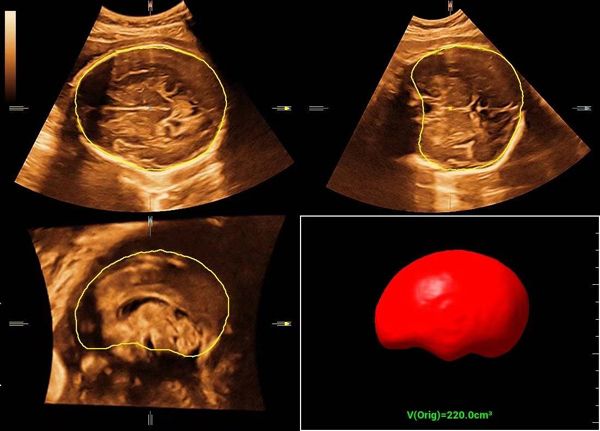

颅内容积自动测量胎儿颅脑容积全自动评估功能,基于独创的分割算法,实现短时间内的快速分割,一键自动获取更精 准的颅脑容积数据。(上图)